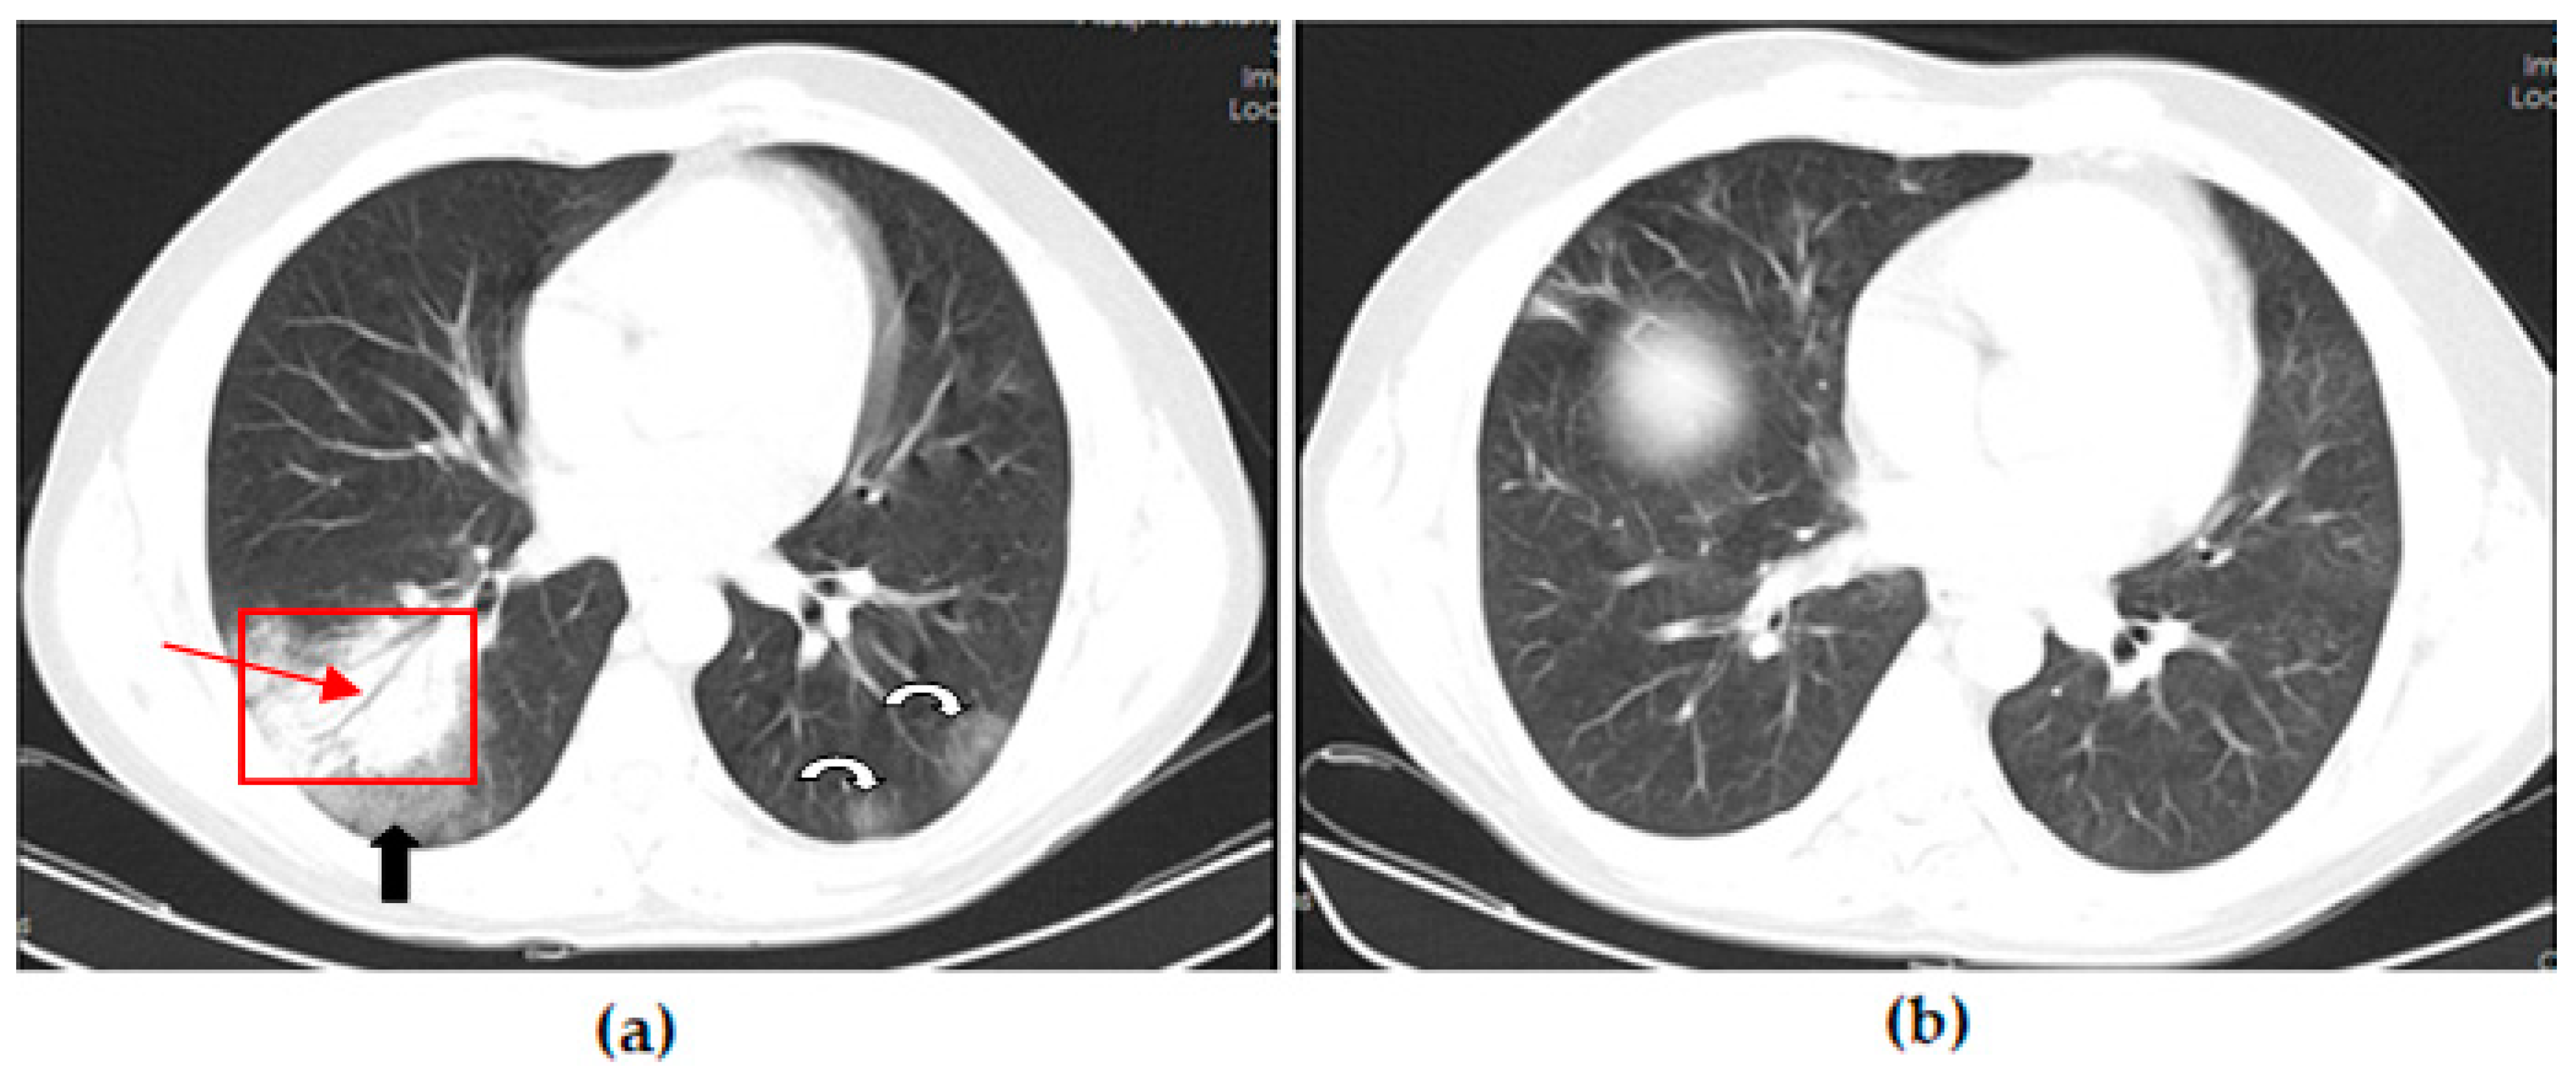

Thoracic CT images of a 45-year-old unvaccinated patient are shown in Figure 2.

Thoracic CT images of a 43-year-old patient vaccinated with a single dose of Biontech are shown in Figure 3.

Figure 2. A 45-year-old unvaccinated male COVID-19 patient presenting with fever with diarrhea for 3 days. (a) The axial thorax CT image shows a patchy ground glass opacity (GGO) appearance in the bilateral lower lobes (red frames) at presentation. (b) The 1st month follow-up axial thorax CT image shows that the GGO appearance of the bilateral lower lobes is lesser than the previous CT scan. Multiple fibrotic parenchymal bands (red arrows) and mild dilatation of the distal bronchial branches (black arrow) were found, especially in the superior segment of the right lower lobe.

Figure 3. A 43-year-old male COVID-19 patient vaccinated with a single dose of Biontech presenting with fever with myalgia for 4 days. (a) The axial thorax CT image shows ground glass opacities (black arrow) around consolidation areas (red frame), including an air bronchogram (red arrow) in the lateral basal segment of the right lower lobe and a patchy GGO appearance in the posterior basal segment of the left lower lobe (white curved arrow) at presentation. (b) The 1st month follow-up axial thorax CT image shows consolidation areas, the GGO appearance regressed, and no pathological findings were found.